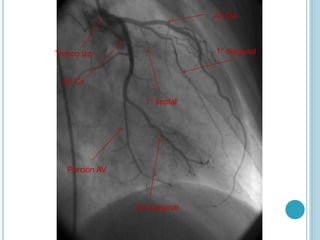

Art Cx

Porción AV

Art marginal

Tronco izq

1° septal

1° diagonal

Art DA

Art Cx Porción AV Artmarginal Tronco izq 1° septal 1° diagonal Art DA